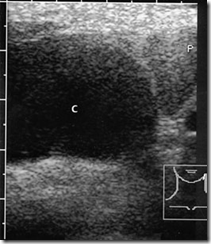

“Ultrasound Pictures” of Infected neck cyst (C) and enlarged cervical lymph nodes (L). a B-mode image before percutaneous aspiration.

“Ultrasound Pictures” CDS shows color pixels in the carotid artery (AC) and jugular vein (V). The cyst was aspirated. P = parotid gland

Sonographic findings:

x Anechoic mass at the border of the sternocleidomastoid muscle

x Cyst: rubbery, compressible; with abscess formation, the contents become

more echogenic

Accuracy of “Ultrasound Pictures” diagnosis Neck Cyst: The cyst is easily detected by sonography, and CDS can positively distinguish it from blood vessels. Neck cysts are rare, and when infected by bacteria they are virtually indistinguishable from a parotid abscess. In these cases the diagnosis can be advanced by aspiration cytology.